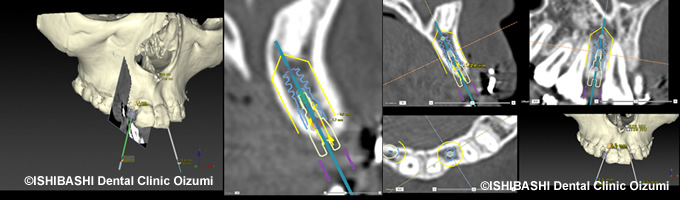

当院では、インプラント治療の前にCTデータをシミュレーションソフト『ノーベルクリニシャン』へと取り込み、患者さんの顎骨の状態や骨質を精密に診断した上で、使用するインプラントの種類や径、長さ、角度などを決定していきます。このコンピュータシミュレーションによってインプラント治療をより正確に施術することを目指します。

当院では、ノーベルバイオケア社の『ノーベルクリニシャン』インプラントシステムを使用し、CTデータによる正確な診断、設計を行っています。

『ノーベルクリニシャン』とは、『インプラント療法をより正確にサポートし、治療を行う為のシステム』です。

まず、CTスキャンにより患者様の顎骨の形を完全に再現した3D情報を使用します。

これにより、事前に『インプラントを埋入するための十分な骨があるか』『どの角度で、太さ何ミリのインプラントを、深さ何ミリまで入れれば良いか』といった、事前の情報が分かります。

また、この情報を元に綿密な手術計画が立てられるので、普通のインプラント治療よりも手術にかかる時間が少なくなります。

そして、計画が綿密であるため、手術の前に患者様にしっかりとしたご説明ができ、手術をお受けいただけます。